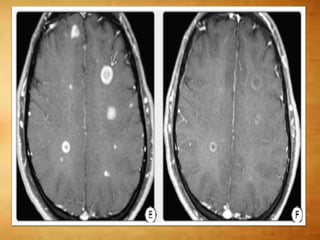

T1 C+

 Active demyelination - transient enhancement

- Punctate, nodular, linear, and rim patterns are

seen

 Large tumefactive lesions – horseshoe

enhancement- open nonenhancing segment

facing the cortex